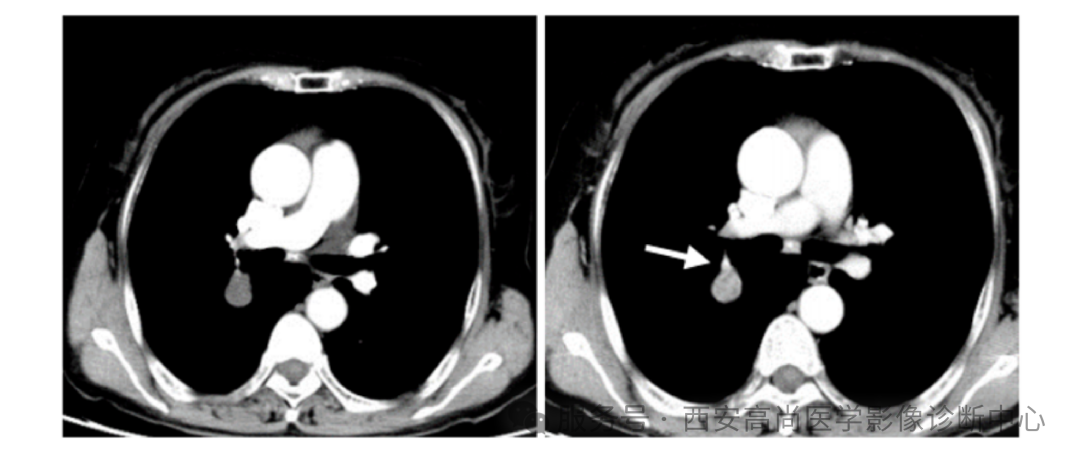

检查所见:右肺中叶见不均匀团块状软组织病变,大小约 8.0 cm×6.3 cm×7.0 cm,右肺中叶支气管完全闭塞,肿块呈高低混杂密度,边界较为光整,其内见点状钙化灶,呈不均匀放射性摄取异常增高,SUV 最大值介于 2.6-6.0。

影像学诊断:右肺中叶不均匀团块状软组织病变,肿块呈高低混杂密度,呈不均匀 FDG 代谢增高,结合病理,考虑为肺低度恶性肿瘤可能(孤立性纤维瘤?)建议穿刺病理检查明确。

研究表明18 F-FDG PET 上 PSP 可表现异常放射性浓聚,一般为轻到中度 ,影响 PSP 18 F-FDG 摄取因素尚不清楚,有学者研究认为 浓聚的高低可能与肿瘤大小相关。瘤体小于 2.5,FDG 呈轻度摄取增高。瘤体大于 4 cm,SUV 最大值>2.5。